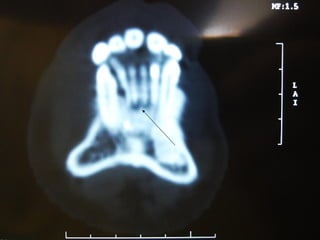

Eliminación de focos sépticos en bloque en paciente con osteitis

mandibular crónica

Osteitis

Imagen microscópica de osteitis, inicialmente existe una etapa de

osteoclastosis seguida por regeneración. No siempre el hueso

regenera en su totalidad y sigue el curso de cualquier inflamación

dejando un area de tejido fibroso que con el tiempo puede

calcificarse (hueso denso)

Manejo con antibióticos obligado

Revisión periódica